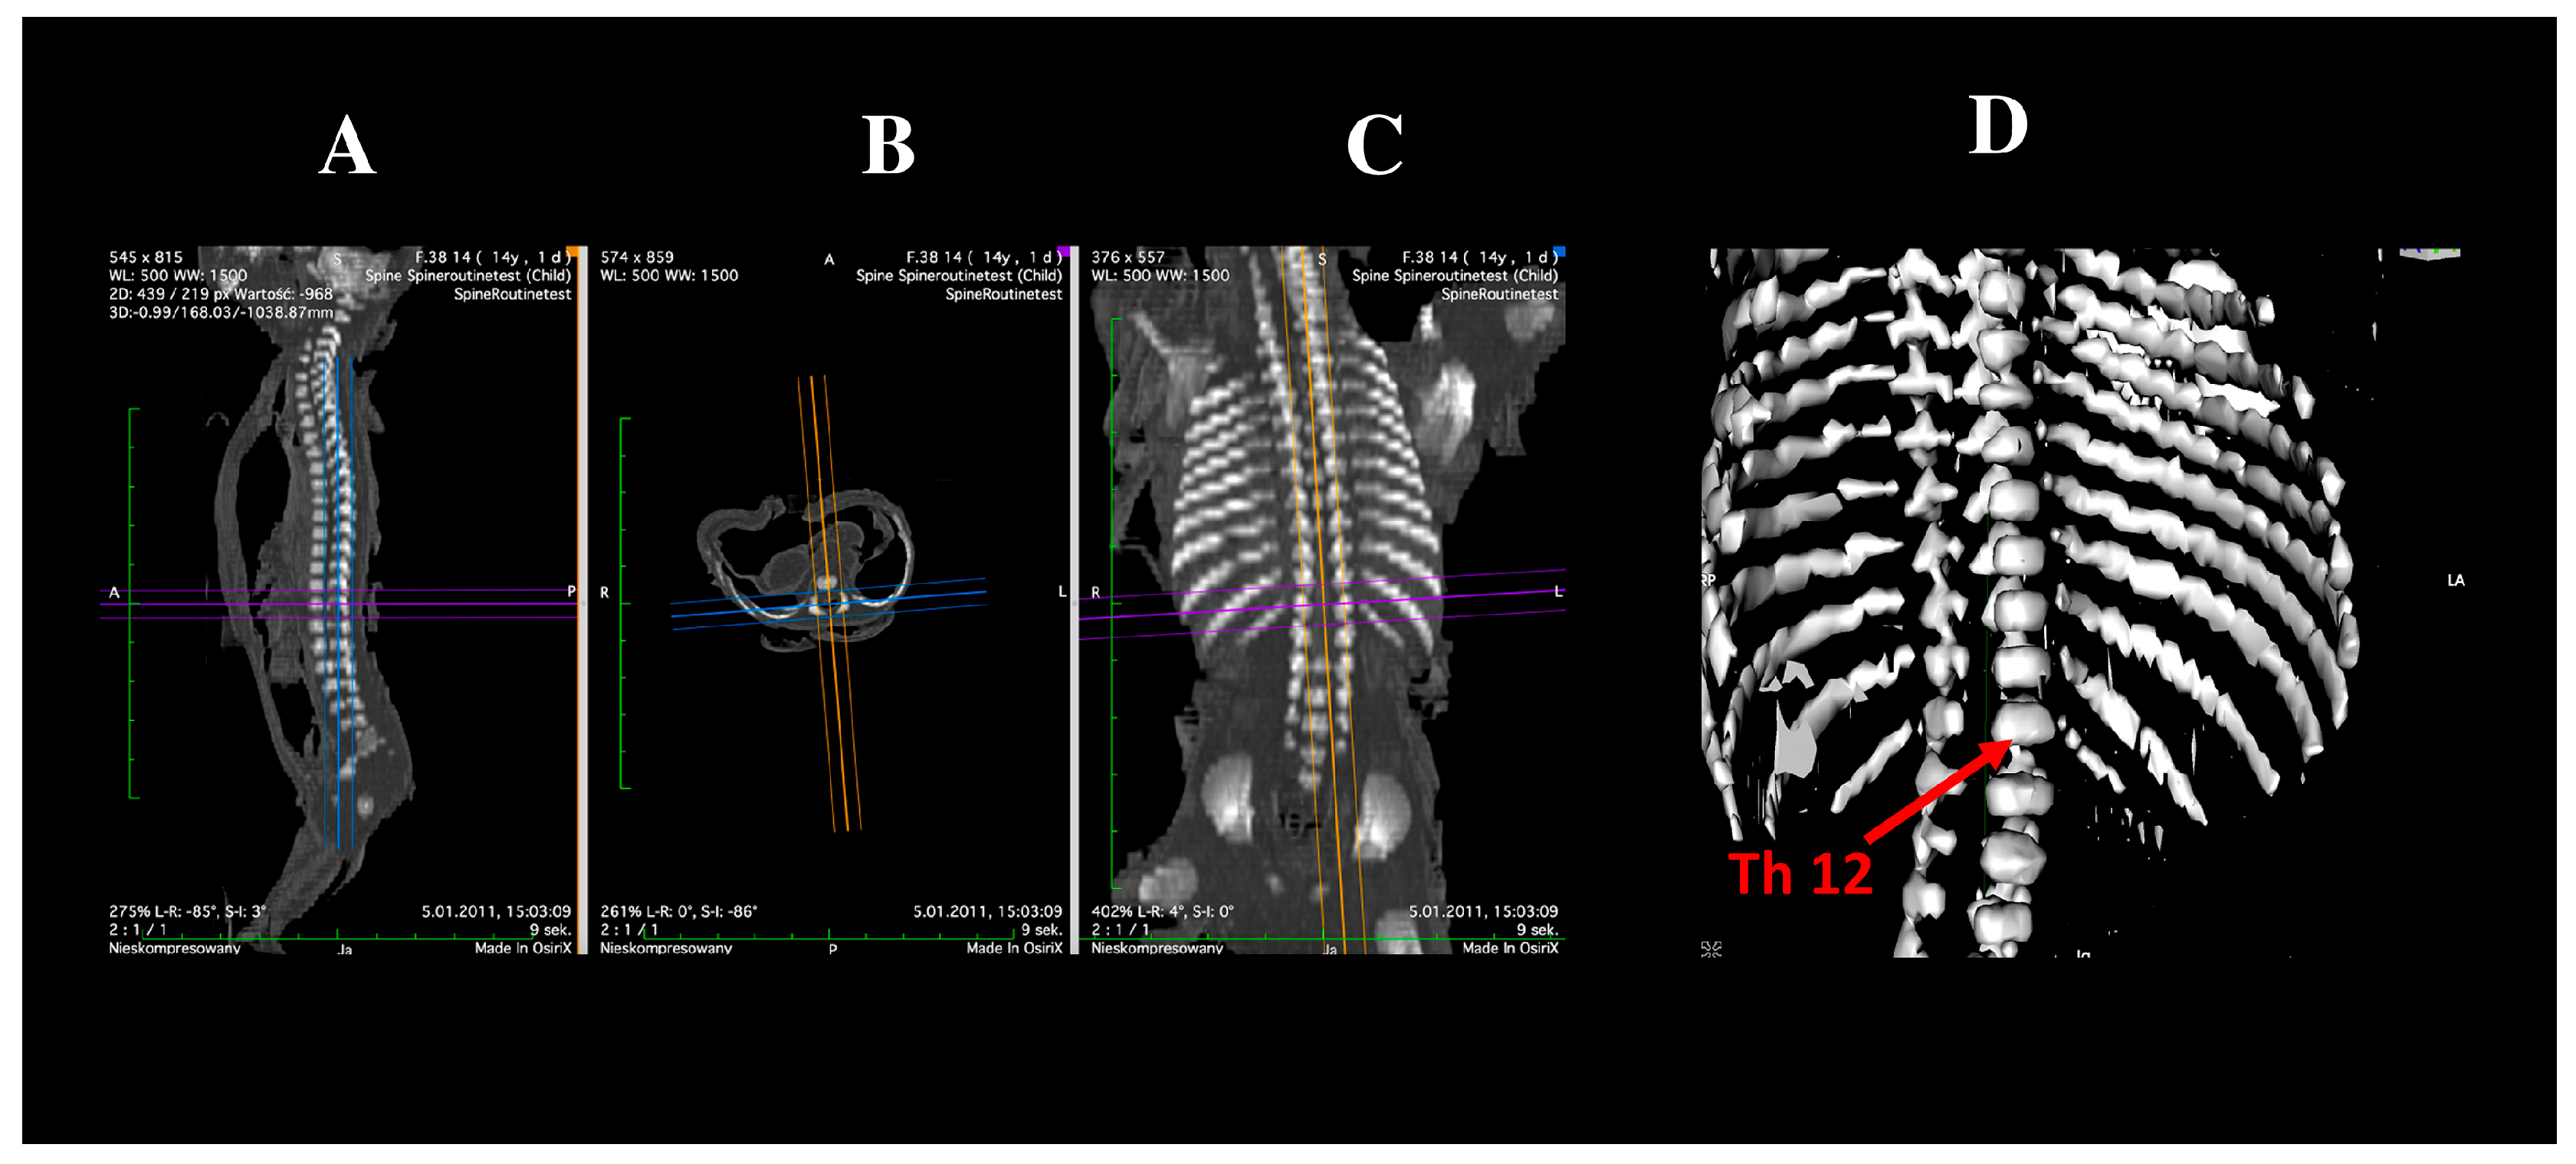

2.2. Morphometric Measurements and Assessment of Ossification Centers

- Volume of each ossification center—computed using advanced diagnostic imaging software that enables three-dimensional reconstruction based on spatial position and tissue X-ray attenuation (Figure 2).